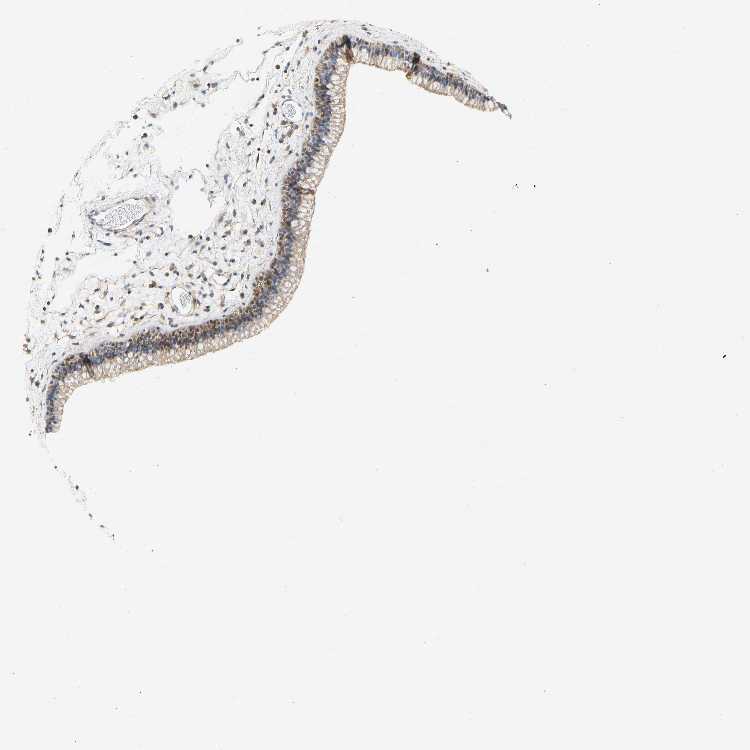

TISSUE PRIMARY DATA NASOPHARYNX Show tissue menu

NASOPHARYNX - Antibody stainingi

Antibody staining in the annotated cell types in the current human tissue is reported as not detected, low, medium, or high, based on conventional immunohistochemistry profiling in selected tissues. This score is based on the combination of the staining intensity and fraction of stained cells.

Each image is clickable and will lead to virtual microscopy that enables deeper exploration of all samples and also displays staining intensity scores, fraction scores and subcellular localization as well as patient and tissue information for each sample.

Antibody HPA014788Antibody HPA018176

Respiratory epithelial cells MediumLow